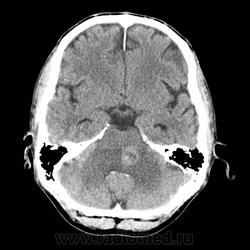

КТ ГМ+C Субтенториальное объемное образование в стволе головного мозга (мост)

Мужчина 46 лет. Поступил с подозрением на ОНМК. Жалобы на шаткую походку, снижение зрения. Мост содержит ядра ЧМН (V, VI, VII, VIII). Для невриномы и менингиомы не  характерна локализация. Узловое, экспансивно растущее образование, интенсивно накапливает КВ. DDs: Кавернозная ангиома, mts.

Ну да, перифокального отека нет, лишь IV желудочек компремирован. МРТ точно рассудит.

Да как то не выражен, может незначительный, IV желудочек не резко  деформирован и сужен.

Отека то может  и не быть, а вот границы у этой опухоли довольно таки четкие для mts, хотя... будем искать или исключать основную опухоль.